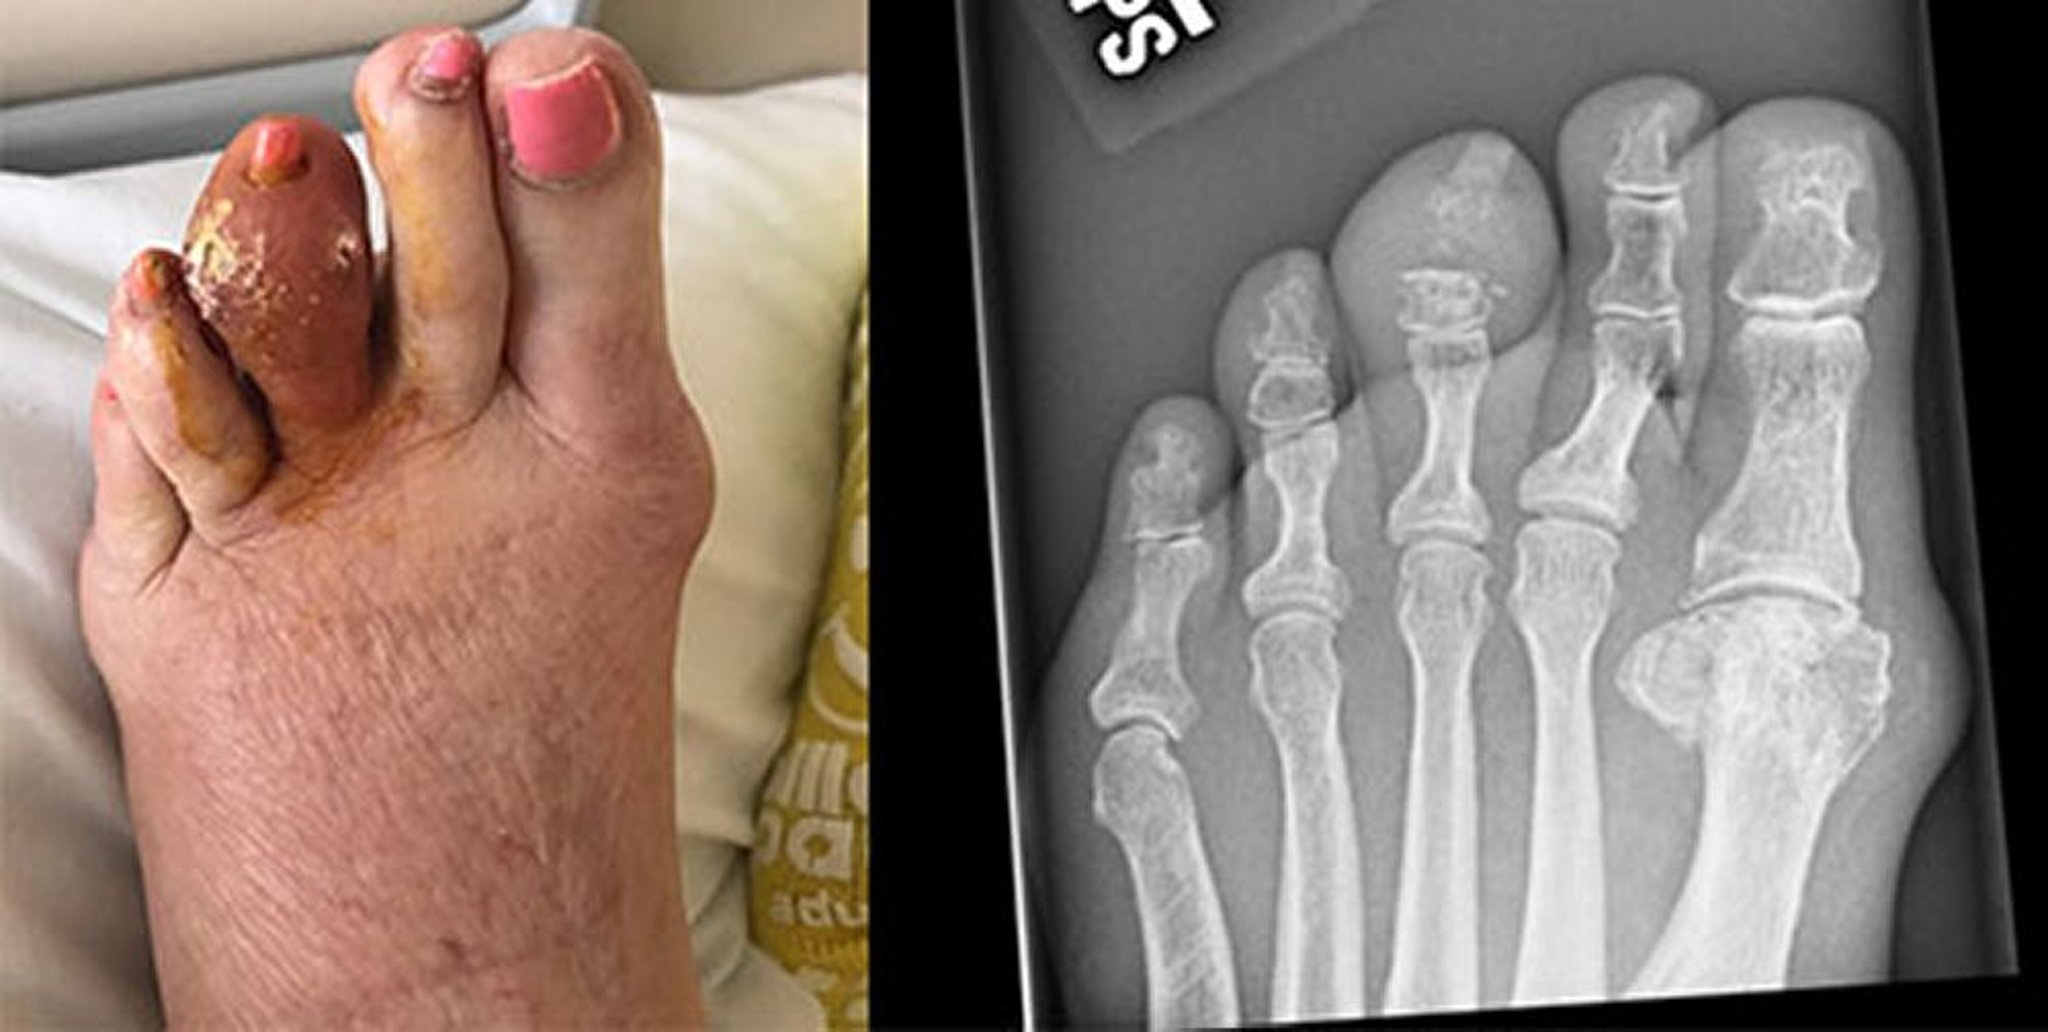

中趾の痛風

この写真には,左第3趾の大きな痛風結節が写っており,結節は崩壊し,硬化した尿酸を放出している。右のX線写真には,中節骨および遠位指節間関節のびらんが写っている。

Images courtesy of Brian F.Mandell, MD.